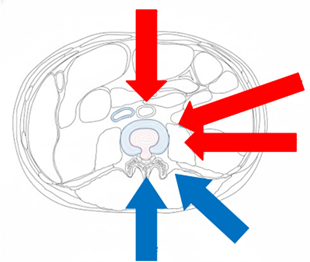

相較於傳統脊椎手術需分部位、分階段進行,住院與復原時間較長,臺中市醫引進的「前位或前側位脊椎融合手術」搭配 3D 電腦導航系統,可於同一次手術中完成多節段融合與多部位重建。手術採「間接減壓」方式,不需直接進入脊椎腔,大幅降低神經損傷風險。

手術以間接減壓的方式,從後腹腔進入(紅色箭頭),有別傳統從脊椎腔(藍色箭頭)切入,因此能夠不破壞骨骼不撥弄脊椎神經,大幅減低神經損傷機率。官方提供